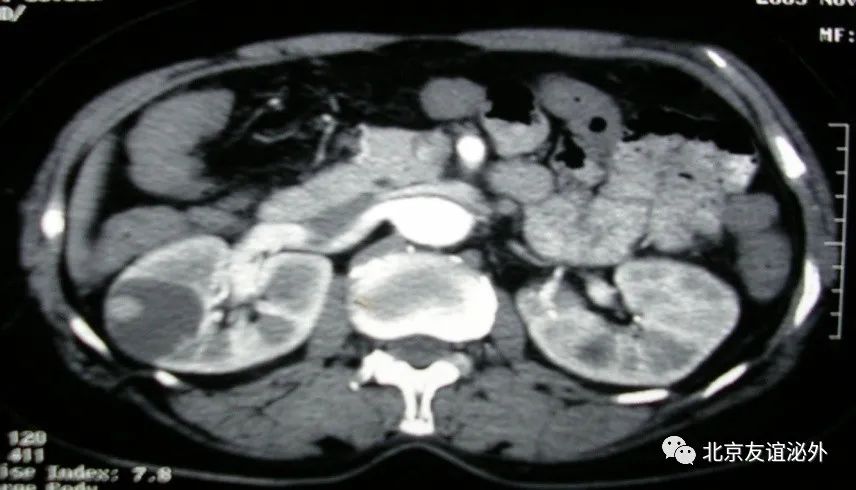

图4. Bosniak IIF级良性囊肿(囊肿伴乳头状瘤)